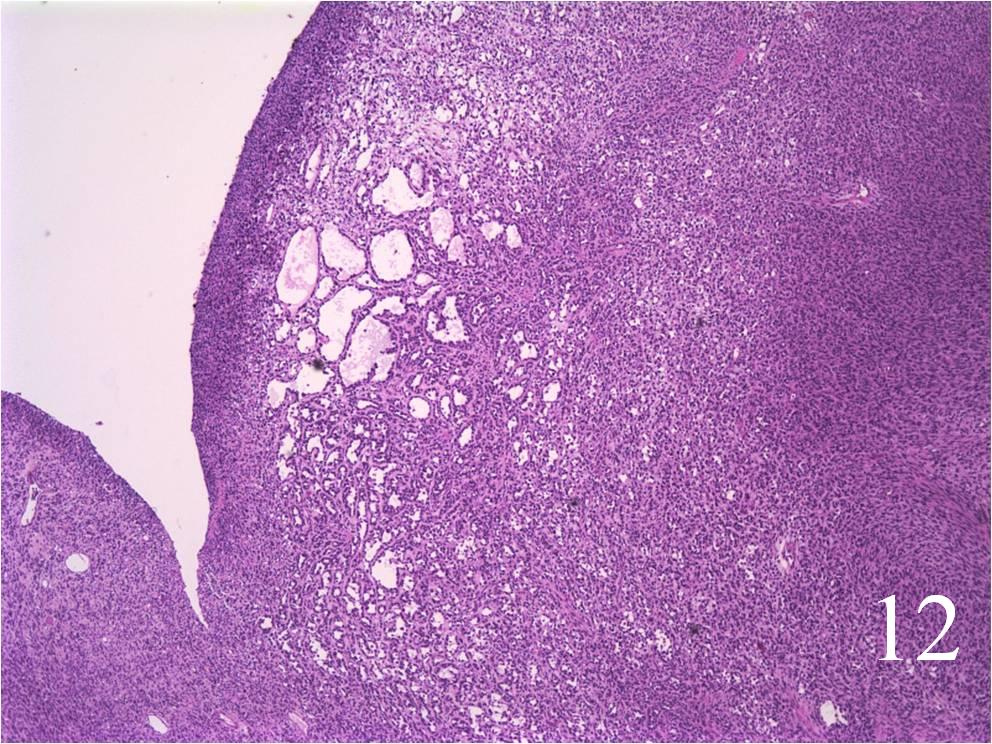

- Embryonal:

- Small round blue cells (Fig. 12-15)

- Round, oval, polygonal cells

- Fibrotic/myxoid stroma

- Rhabdomyoblast: well differentiated will have cross striations